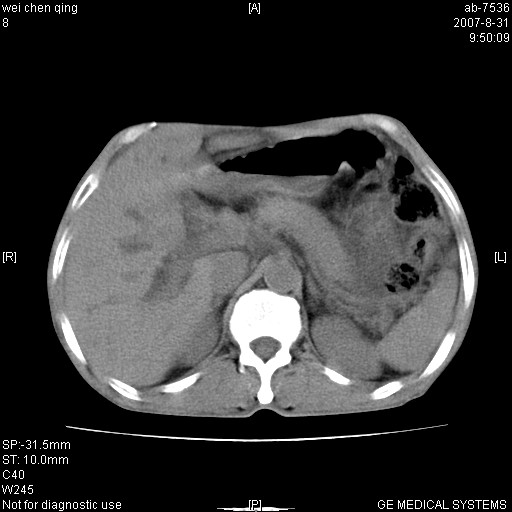

以下是引用zyyzzy在2007-8-31 14:34:00的发言:[br]该病人肝内胆管扩张,胆囊及胆总管未见明显扩张。在倒数第9层图像上可看到左右肝管结合部(肝总管)有软组织影,此处应薄层扫描。考虑肝总管占位(ca)、腹水。[br]